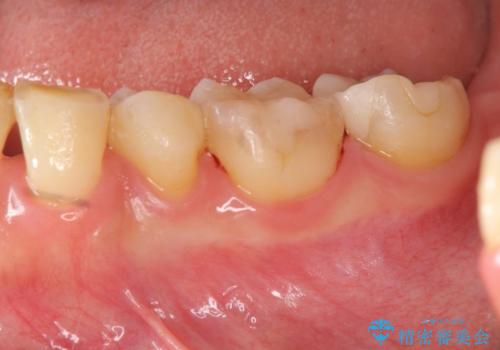

健全な歯を削らないように拡大鏡下で丁寧に虫歯を除去することで神経を温存し精密なセラミック治療を行うことができました。

- 15.4万円(セラミックインレー×2)費用は治療当時の料金となります